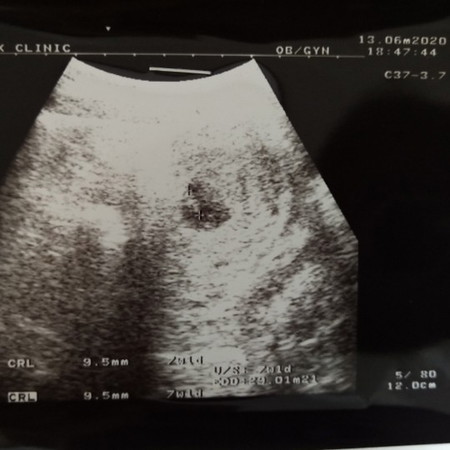

อายุครรภ์ในใบซาว7W1D

อายุครรภ์ในใบซาว7W1D ในแอฟ6W5D เจอตัวเด็กน้อยพร้อมหัวใจกระพริบๆแล้วจ้า❤